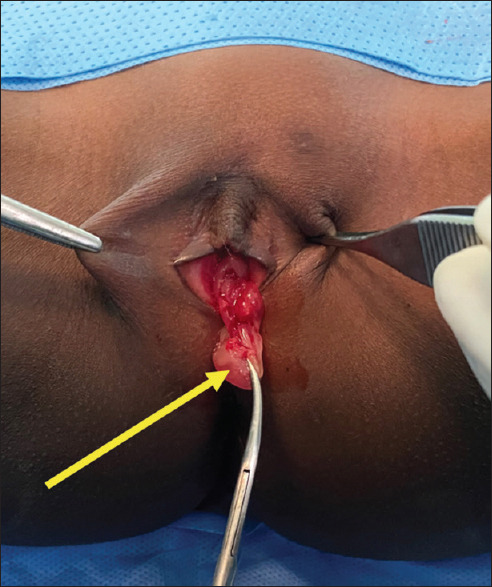

摘要:阴道分泌物是月经前少女常见的妇科疾病。然而,当阴道分泌物持续存在时,必须怀疑阴道内异物(FB)。我们报告了一例转诊的 4 岁女孩,她有 5 个月的持续恶臭阴道分泌物病史。临床检查证实其阴道有脓性分泌物,并伴有阴道肉芽肿。数字直肠检查时,通过直肠前壁摸到一个阴道内的硬物。盆腔 X 光平片显示有一个不透射线的物体,超声波检查证实了该物体在阴道内的位置。患者接受了肉芽肿切除术、FB切除术和抗生素治疗。12 个月的随访结果无异常。

Abstract: Vaginal discharge is a common gynaecologic complaint in pre-menarchal girls. However, an intravaginal foreign body (FB) must be suspected when it is persistent. We report the case of a referred 4-year-old girl with a 5-month history of persistent foul-smelling vaginal discharge. Clinical examination confirmed purulent vaginal discharge, along with a vaginal granuloma. A hard, intravaginal object was felt through the anterior rectal wall on digital rectal examination. A plain pelvic X-ray revealed a radiopaque object whose intravaginal position was confirmed by ultrasonography. The patient underwent granuloma excision plus FB removal and antibiotic treatment. The 12-month follow-up was unremarkable.